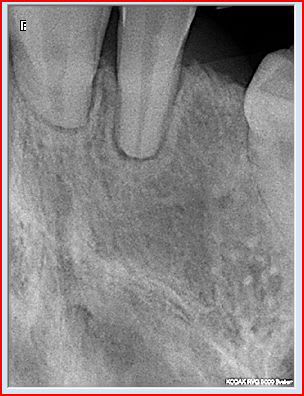

on enleve l'arc de niti . UN rx rétroalvéolaire montre une résorption radiculaire et alvéolyse au niv des 4 INCISIFS; dans ce cas le plus inquietant; quelle la coduite à tenir et quelle est la faute commise?

voici la rx avant trt et aprés trt d'ortho.

la rx panoramique c'est avant le ttt el les rx rétroalvélaire aprés le ttt.